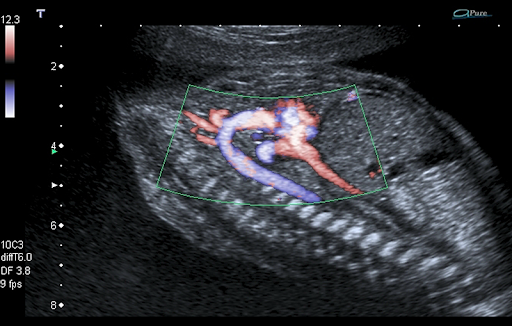

ADF - Advanced Dynamic Flow™* позволяет визуализировать мельчайшие кровеносные сосуды и регистрировать кровоток с непревзойденной точностью и детализацией.

Volume Imaging* Suite включает в себя полный набор режимов обработки изображений (рендеринг поверхности, Multiview и MPR), что позволяет получать большой объем данных при уменьшении времени, требуемого для проведения обследования.